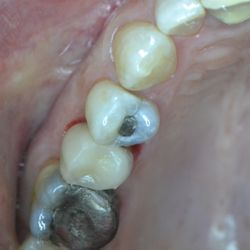

Ο κάτω γομφίος σε αυτή την νεαρή ασθενή έχει απονευρωθεί.

Για να εξασφαλίσουμε την καλή πρόγνωση του δοντιού και ταυτόχρονα την προστασία του από πιθανό κάταγμα, αποφασίστηκε η τοποθέτηση ενός επενθέτου εργαστηριακής σύνθετης ρητίνης.

Η διαδικασία ολοκληρώθηκε σε 2 ραντεβού, ενώ ο τροχισμός του δοντιού διατηρήθηκε στο ελάχιστο δυνατό.

Η εναλλακτική λύση θα ήταν να τροχιστεί εντελώς το δόντι και να τοποθετηθεί μια στεφάνη, οδηγώντας όμως έτσι σε αφαίρεση μεγάλης ποσότητας οδοντικής ουσίας.